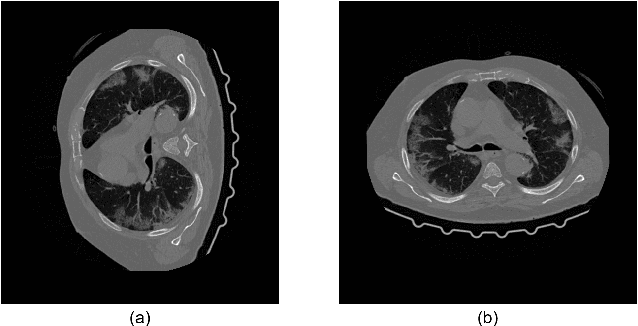

We present a deep-learning based computing framework for fast-and-accurate CT (DL-FACT) testing of COVID-19. Our CT-based DL framework was developed to improve the testing speed and accuracy of COVID-19 (plus its variants) via a DL-based approach for CT image enhancement and classification. The image enhancement network is adapted from DDnet, short for DenseNet and Deconvolution based network. To demonstrate its speed and accuracy, we evaluated DL-FACT across several sources of COVID-19 CT images. Our results show that DL-FACT can significantly shorten the turnaround time from days to minutes and improve the COVID-19 testing accuracy up to 91%. DL-FACT could be used as a software tool for medical professionals in diagnosing and monitoring COVID-19.